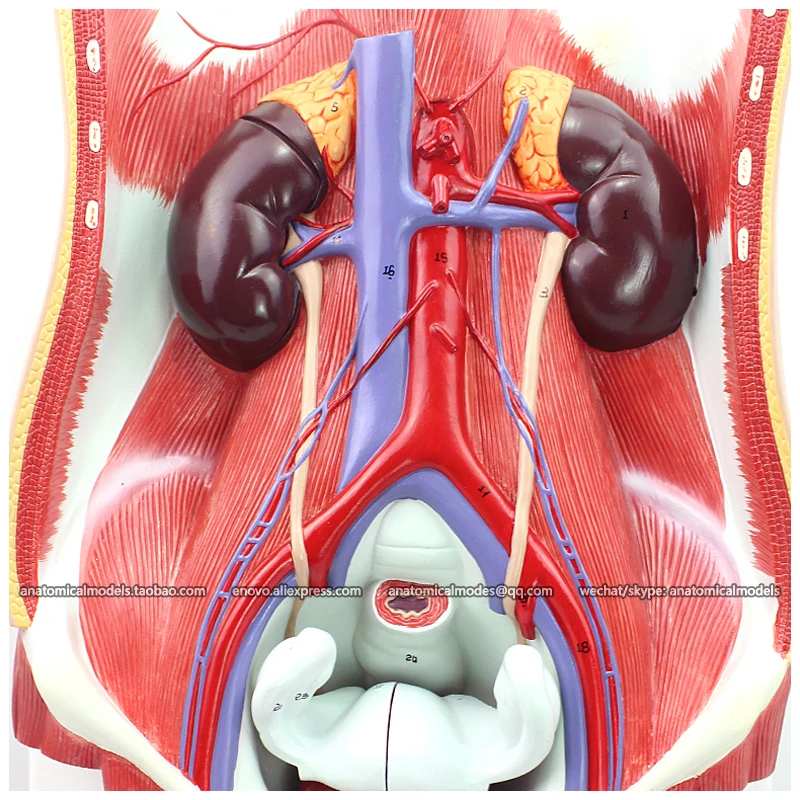

13,882.40 руб.

12426 / Removable Organ Anatomy Urinary System Model on Board, Medical Science Educational Anatomical Models

aliexpress.com